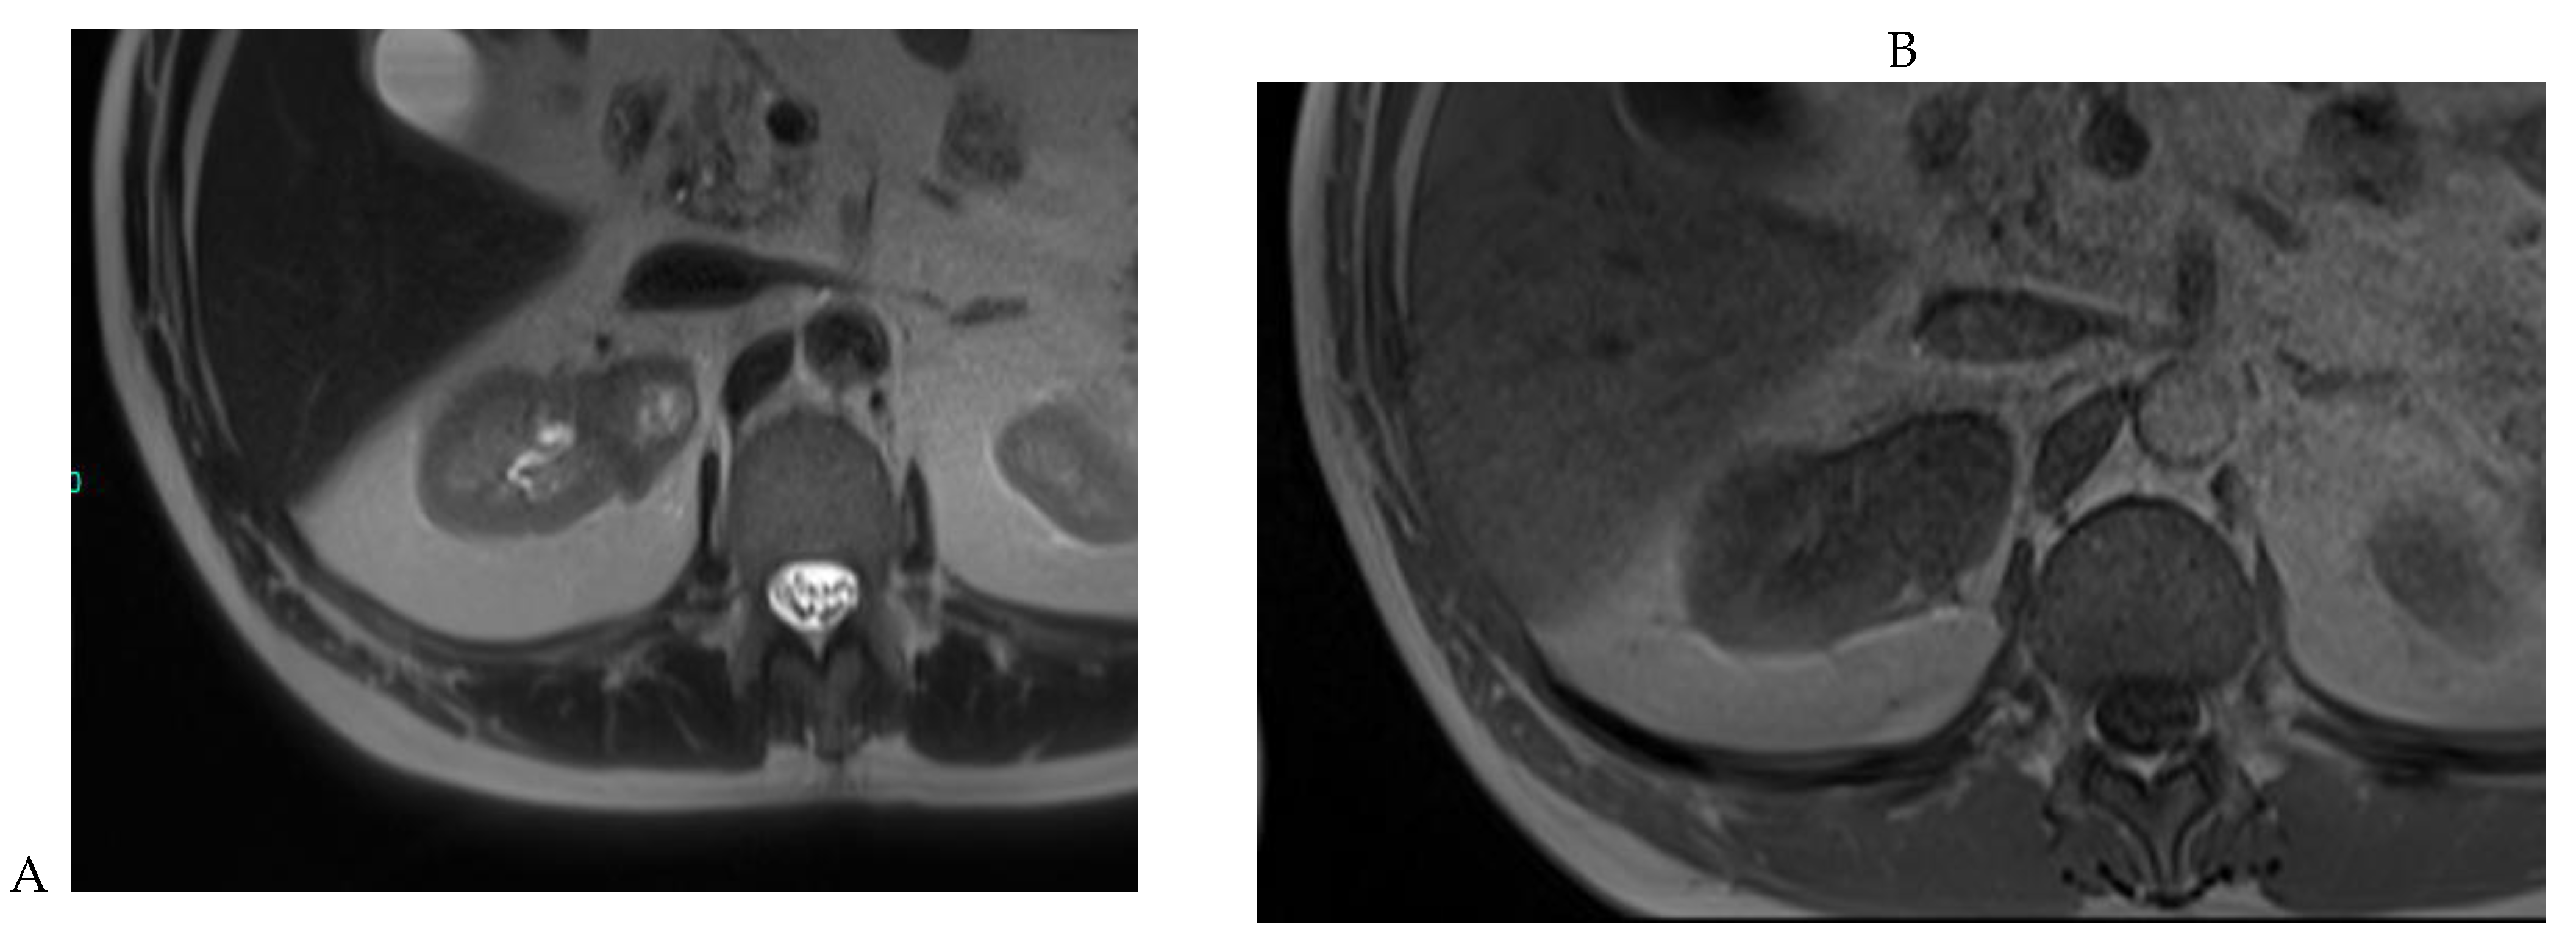

Figure 5.

Clear cell renal cell carcinoma in the right kidney of a 52-year-old-man. (A) Coronal T2-weighted fast SE image shows a large heterogeneous mass with areas of high signal intensity compared with renal parenchyma. Transverse in-phase (B,C) opposed-phase MR images show a subtle signal loss on the opposed-phase image. (D) The ADC map is heterogeneous with predominant areas of restriction of tumor diffusion. Transverse gadolinium-enhanced T1-weighted gradient-echo spoiled MR images in (E) corticomedullary, (F) nephrographic, (G) and delayed phase images show intense and rapid peripheral enhancement during the arterial and nephrographic phases followed by a rapid washout of contrast on the delayed phase. Central necrotic areas do not enhance. (H) Macroscopic view of the lesion after radical nephrectomy. The lesion appears heterogeneous. Courtesy of Pr S. Ferlicot, Department of Pathology, Bicêtre Hospital.